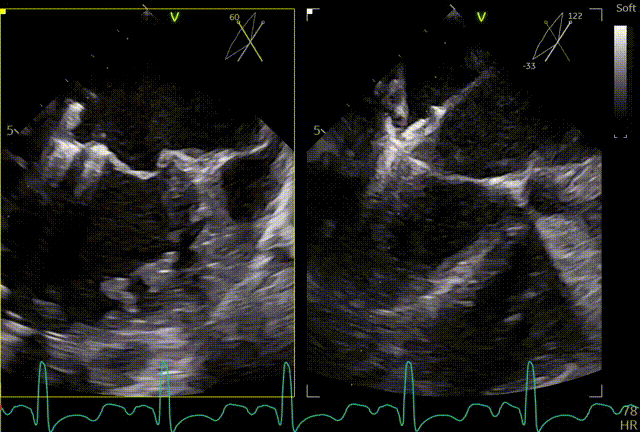

术前心超团队王蓓教授以及余婵教授对患者的瓣膜解剖情况进行了详细的评估:

① 二尖瓣后叶广泛栓系,前后叶对合不良,二尖瓣重度关闭不全,Carpentier分型Ⅲb,反流程度4+;

② 画迹法显示二尖瓣瓣口面积5.25cm²,平均跨瓣压差4.2mmHg;

③ 二尖瓣前叶(A1)长度28.5mm,二尖瓣后叶(P1)长度: 10.4mm;二尖瓣前叶(A2)长度28.4mm,二尖瓣后叶(P2)长度: 12.7mm二尖瓣前叶(A3)长度22.6mm,二尖瓣后叶(P3)长度: 11.5mm;

④ 3区前后叶对合gap 4.5mm,2区前后叶对合gap 3mm。

术前TEE及左房压

1区

2区

3区